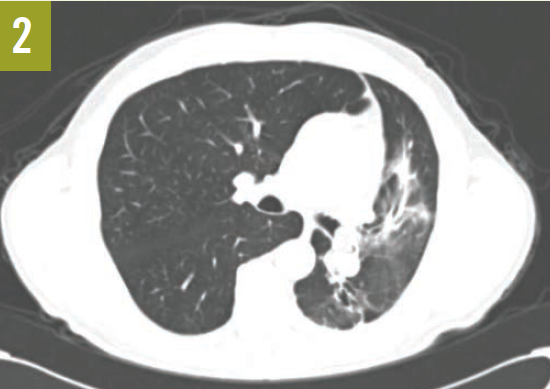

Upon admission, a chest radiograph revealed hyperlucency of the right hemithorax with a right basilar infiltrate (Figure 1). Computed tomography (CT) of the chest showed extensive unilateral bullous emphysema involving the entire right lung from apex to base (Figure 2). The emphysema was confined to one side and was so severe and voluminous that the mediastinum was pushed far away from its midline alignment with the sternum into the left hemithorax, resulting in compression and atelectasis of the left lung. There was also a right-sided pneumonia superimposed on the background of emphysema.

Figure 2. A CT scan of the chest at the level of the carina showed severe and voluminous bullous emphysema of the right lung; the mediastinum is pushed far away from its midline alignment with the sternum into the left hemithorax, and a right basal pneumonia is present.